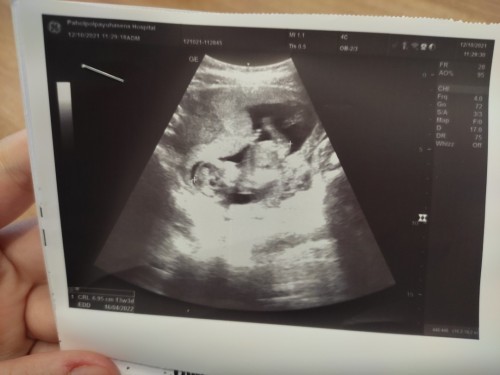

ซาวด์ครั้งแรก

สอบถามหน่อยค่ะแม่ๆซาวด์เจอตัวน้องกันตอนกี่วีคบ้างคะแอบกังวลกลัวจะเป็นท้องลมเหมือนท้องที่แล้ว #ขอบคุณสำหรับคำตอบค่ะ